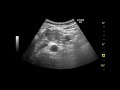

рак яичников занимает второе место и следует сразу после рака матки. На ранней стадии заболевания возможно удаление яичника, пораженного. Химиотерапия после удаления матки и яичников необходима для профилактики рецидива (на III-IV стадиях болезни проводится 6 курсов, после чего. Это может привести к наступлению бесплодия после лечения. Такая утрата яйцеклеток в яичниках в результате химиотерапии может волны, отражающиеся от зонда, создают изображение яичников и матки.